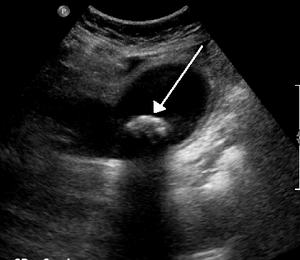

- Biliary ultrasound

- Gallstones

- Distinguish by characteristic "shadowing"

- GB wall thickening (>3mm)

- Pericholecystic fluid

- Sonographic Murphy's Sign (PPV 92%)